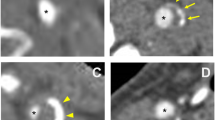

The degree of luminal stenosis, plaque thickness, surface ulceration and remodeling index (RI = the maximum wall thickness at the most stenotic site/the wall thickness at the nearby disease-free site) were calculated or identified. Positive soft plaque was defined as maximum soft plaque thickness >2 mm [25], and a positive remodeling index was reported as RI ≥ 1.1 [26]. The mean plaque Hounsfield unit (HU) was defined as the average HU in the region between the lumen and outer wall contour across the whole plaque volume [27]. Ulceration was defined as irregular concavities with a minimum depth of 1 mm on any plane [28, 29] (Fig. 1). The presence of calcification and the location and number of calcific nodules were recorded and categorized as either surface (Fig. 2), deep or mixed calcification. Superficial calcification was defined as a calcified nodule located at the intimal-lumen interface or close to the lumen [30]. Deep calcification was defined as a calcified nodule located at the media/adventitia border or close to the adventitia. The presence of both deep and superficial calcification was regarded as a mixed category. According to the maximum thickness, calcification was classified as either thick (≥ 2 mm) or thin (< 2 mm). A distinction was also made between single and multiple nodules (Fig. 3). All parameters and characteristics were independently evaluated by two experienced radiologists, both of whom were blinded to patient clinical presentation and histopathology findings.

CTA and pathological image showing multiple calcifications and IPH on the internal carotid artery. A and B MPR images of the plaque with multiple calcified nodules within the plaque (arrows; B is an axial view of A at the level with calcifications). C Eyeball assessment of the CEA specimen showing IPH (arrow). D Hematoxylin and eosin (×16) stain showing IPH (arrow)